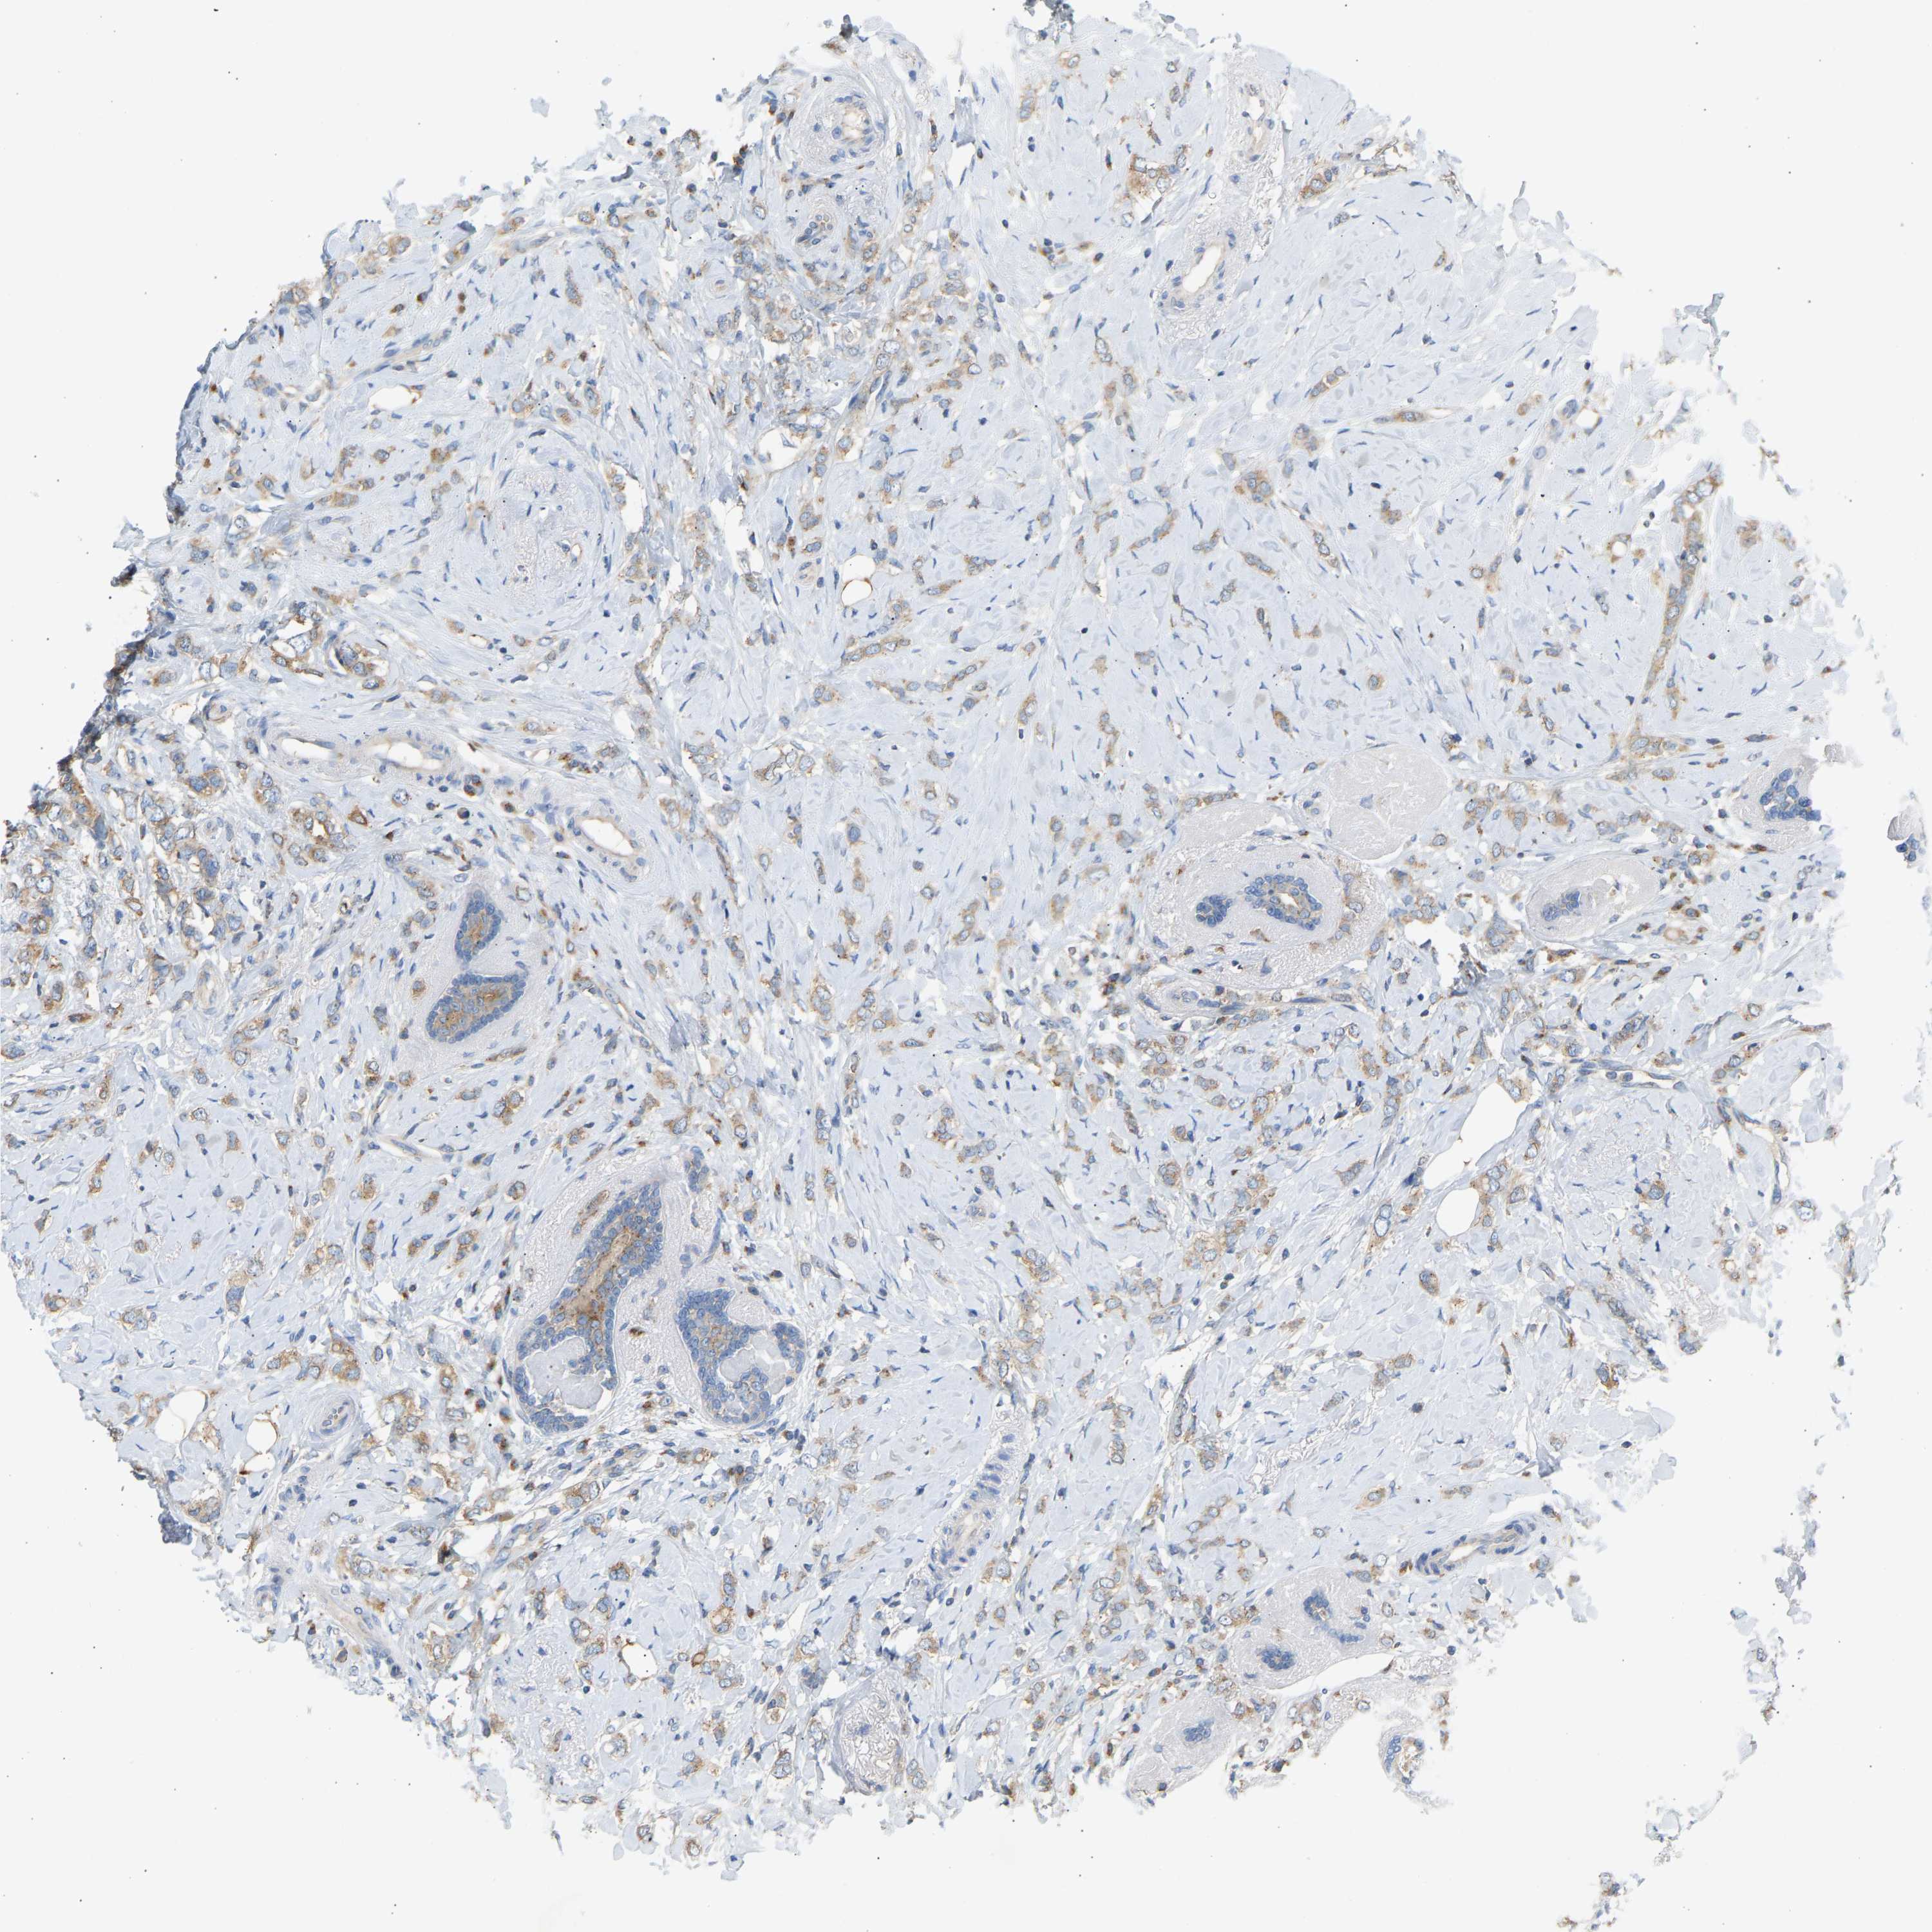

CANCER BREAST CANCER Show tissue menu

Breast cancer

Human cancer

TRIM50 is not prognostic in Breast Invasive Carcinoma (TCGA)